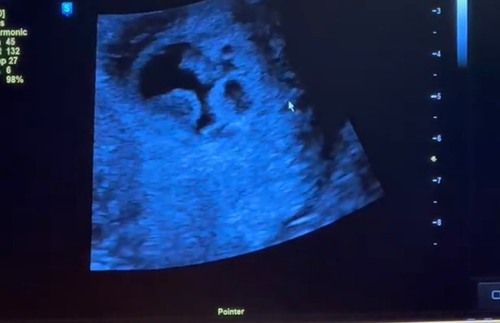

Ik ben sinds april in verwachting en met de medische 13 weken echo is er een afwijkende placenta gezien. De helft van de placenta leek op een gatenkaas en de andere helft leek goed.

De echoscopiste durfde er niks over te zeggen, mijn verloskundige liet het woord mola zwangerschap vallen. We werden doorverwezen naar het ziekenhuis voor verder onderzoek. Al met al bleek het geen mola te zijn omdat het om een goed groeiend kindje gaat.

Na vele onderzoeken blijken het cystes/blaasjes in de placenta te zijn. Ook wel placental mesenchymal dysplasia (PMD) genoemd iets wat heel zeldzaam is en geen bekende oorzaak heeft. Bin PMD bestaat een verhoogd risico op vroeggeboorte, groeivertraging en zwangerschapsvergiftiging waardoor we elke 2 weken naar het ziekenhuis moeten voor een uitgebreide echo/controle.